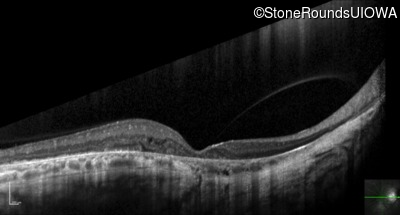

Optical Coherence Tomography - Right - 20/100 sc

Exemplar / OCT Stack